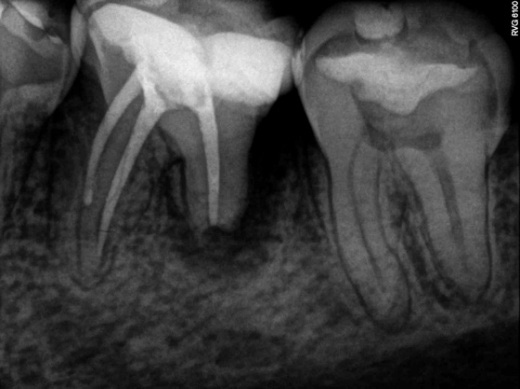

RESUME

A 27-year-old male patient was referred for endodontic evaluation due to palpation discomfort in element 36. During anamnesis it was reported that the tooth had undergone endodontic treatment for two years and since then the tooth had edema by college entrance exam that disappeared and returned (Figure 1A). At radiographic examination, we observed that the previous treatment was unsatisfactory (Figure 1B), confirming the diagnosis of chronic apical abscess.

Figure 1: Clinical aspects (A)

Figure 1: Radiographic aspects (B)